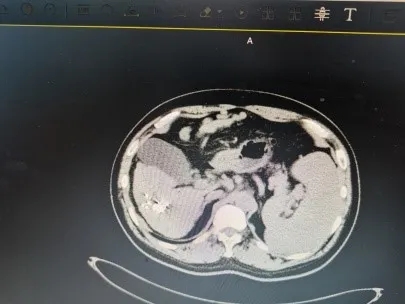

放射治疗分传统的外照射和组织间照射。传统的外照射因放射野大、正常组织耐受量低,其疗效常受到一定的限制。永久粒子植入是通过术中模板,在CT或B超引导下将放射性粒子植入肿瘤内,通过放射性粒子持续释放射线对肿瘤进行杀伤,目前临床常用的永久性植入治疗的粒子为Au、I和Pd,其中I应用最广。放射性粒子植入属于组织间内照射或微创介入性放射治疗,是近几年开展起来的治疗恶性肿瘤的新手段,主要是应用放射性粒子治疗计划系统(TPS)设计治疗方案,在CT或B超引导下将放射性粒子按肿瘤大小、形态植入肿瘤内或受肿瘤侵犯的组织中,通过放射性粒子发出持续、短距离的放射线,使肿瘤组织遭受最大程度的杀伤,而正常组织不受损伤或仅有微小损伤,最终达到治疗目的。作为传统外照射放疗及化疗的一种补充治疗手段,I放射性粒子植入治疗恶性肿瘤具有近期疗效好,副作用小,安全性高的特点。

放射性粒子植入治疗的全称是“放射性粒子组织间插植术”,属于近距离放射治疗(brachytherapy)的范畴,是通过微创方式将多个封装好的具有一定规格、活度的放射源,经施源器或施源导管用多种植入方式直接植入到肿瘤组织内部对肿瘤进行照射,达到治疗目的。

核医学医师依据事先制定的治疗计划,在CT或B超引导下,将长约4毫米、直径0.8毫米的放射性粒子准确植入肿瘤靶区,放射性粒子在体内持续不断发出射线,可使肿瘤接受的剂量明显增加,达到高剂量靶区适形治疗,由于是持续性低剂量率的照射,能够对进入不同分裂周期的肿瘤细胞进行不间断的照射,增加了放射生物效应,提高了放疗疗效。肿瘤组织间植入放射性粒子所产生的射线能量虽然不大,但能持续对肿瘤细胞起作用,不间断的杀伤肿瘤干细胞,经过足够的剂量和半衰期,即可使肿瘤细胞全部失去增殖能力,而达到彻底根除的治疗效果。由于放射性粒子源发射的射线的穿透距离短,有效射程为1.7cm,因此不会损伤到周围正常组织,更不会引起全身症状,在最大限度地杀灭肿瘤细胞的同时,减少对周围正常组织的损伤。